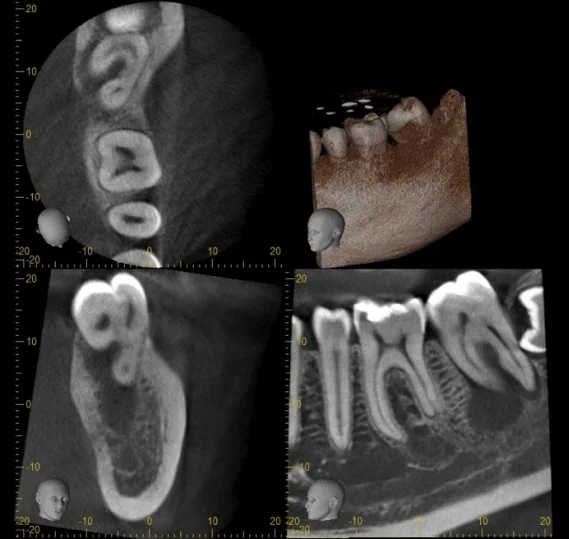

Cone Beam Scanner